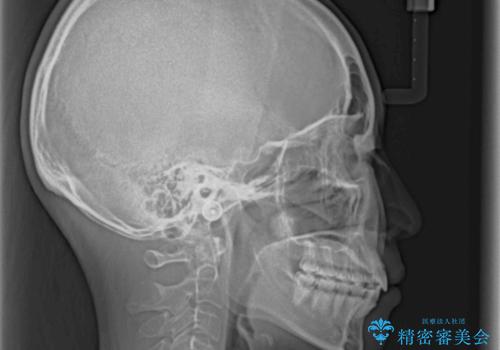

どこまで口元を引っ込めることができるのか、患者様自身も正直分からない部分があったため、少しずつ治療ゴールを変更しながら仕上げていきました。

気になっていた前歯の飛び出した印象は、最終的にはスッキリと引っ込み、大変満足していただきました。